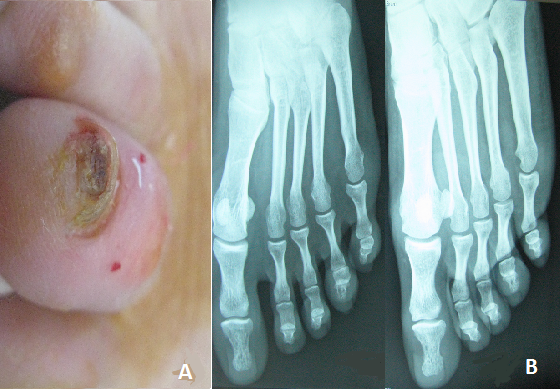

A 29- year- old woman presented to our clinic for subungueal hyperkeratotic lesion of the fourth left toenail. In 1997, she developed systemic sarcoidosis with lung and cutaneous lesions. The patient required gradually tapered systemic corticosteroids for 4 years and methotrexate for 1 year to control lung disease. A few months previously a hyperkeratotic verrucous lesion developed beneath the distal portion of the forth left toenail plate. There was no history of trauma. A biopsy specimen of the nail bed revealed epithelioid granulomas in the dermis without central necrosis. An X-ray of the feet showed severe osteolysis of the terminal phalanx of the forth left toenail. After 2 weeks application, once daily, of hight potency topical steroids, the subungueal hyperkeratosis rapidly improved without relapse after eight months. Nail dystrophy in sarcoidosis is rare. The most common nail changes described in sarcoidosis include thickening of the nail plates associated with fragility and longitudinal ridging , brown discoloration of the nail bed , convex nails and layering , splinter hemorrhage also occur . Such changes are usually associated with lupus pernio and cystic bone change of the phalanx. Our patient did not show lupus pernio like lesions, but radiological examination of the left foot showed bone cyst of the terminal phalanx. Treatment options for nail dystrophy in sarcoidosis include systemic treatment with 10mg/day of prednisone and 200mg/day of hydroxychlorochine sulphate, hight- potency topical steroids application once daily and steroid injections into the nail fold.